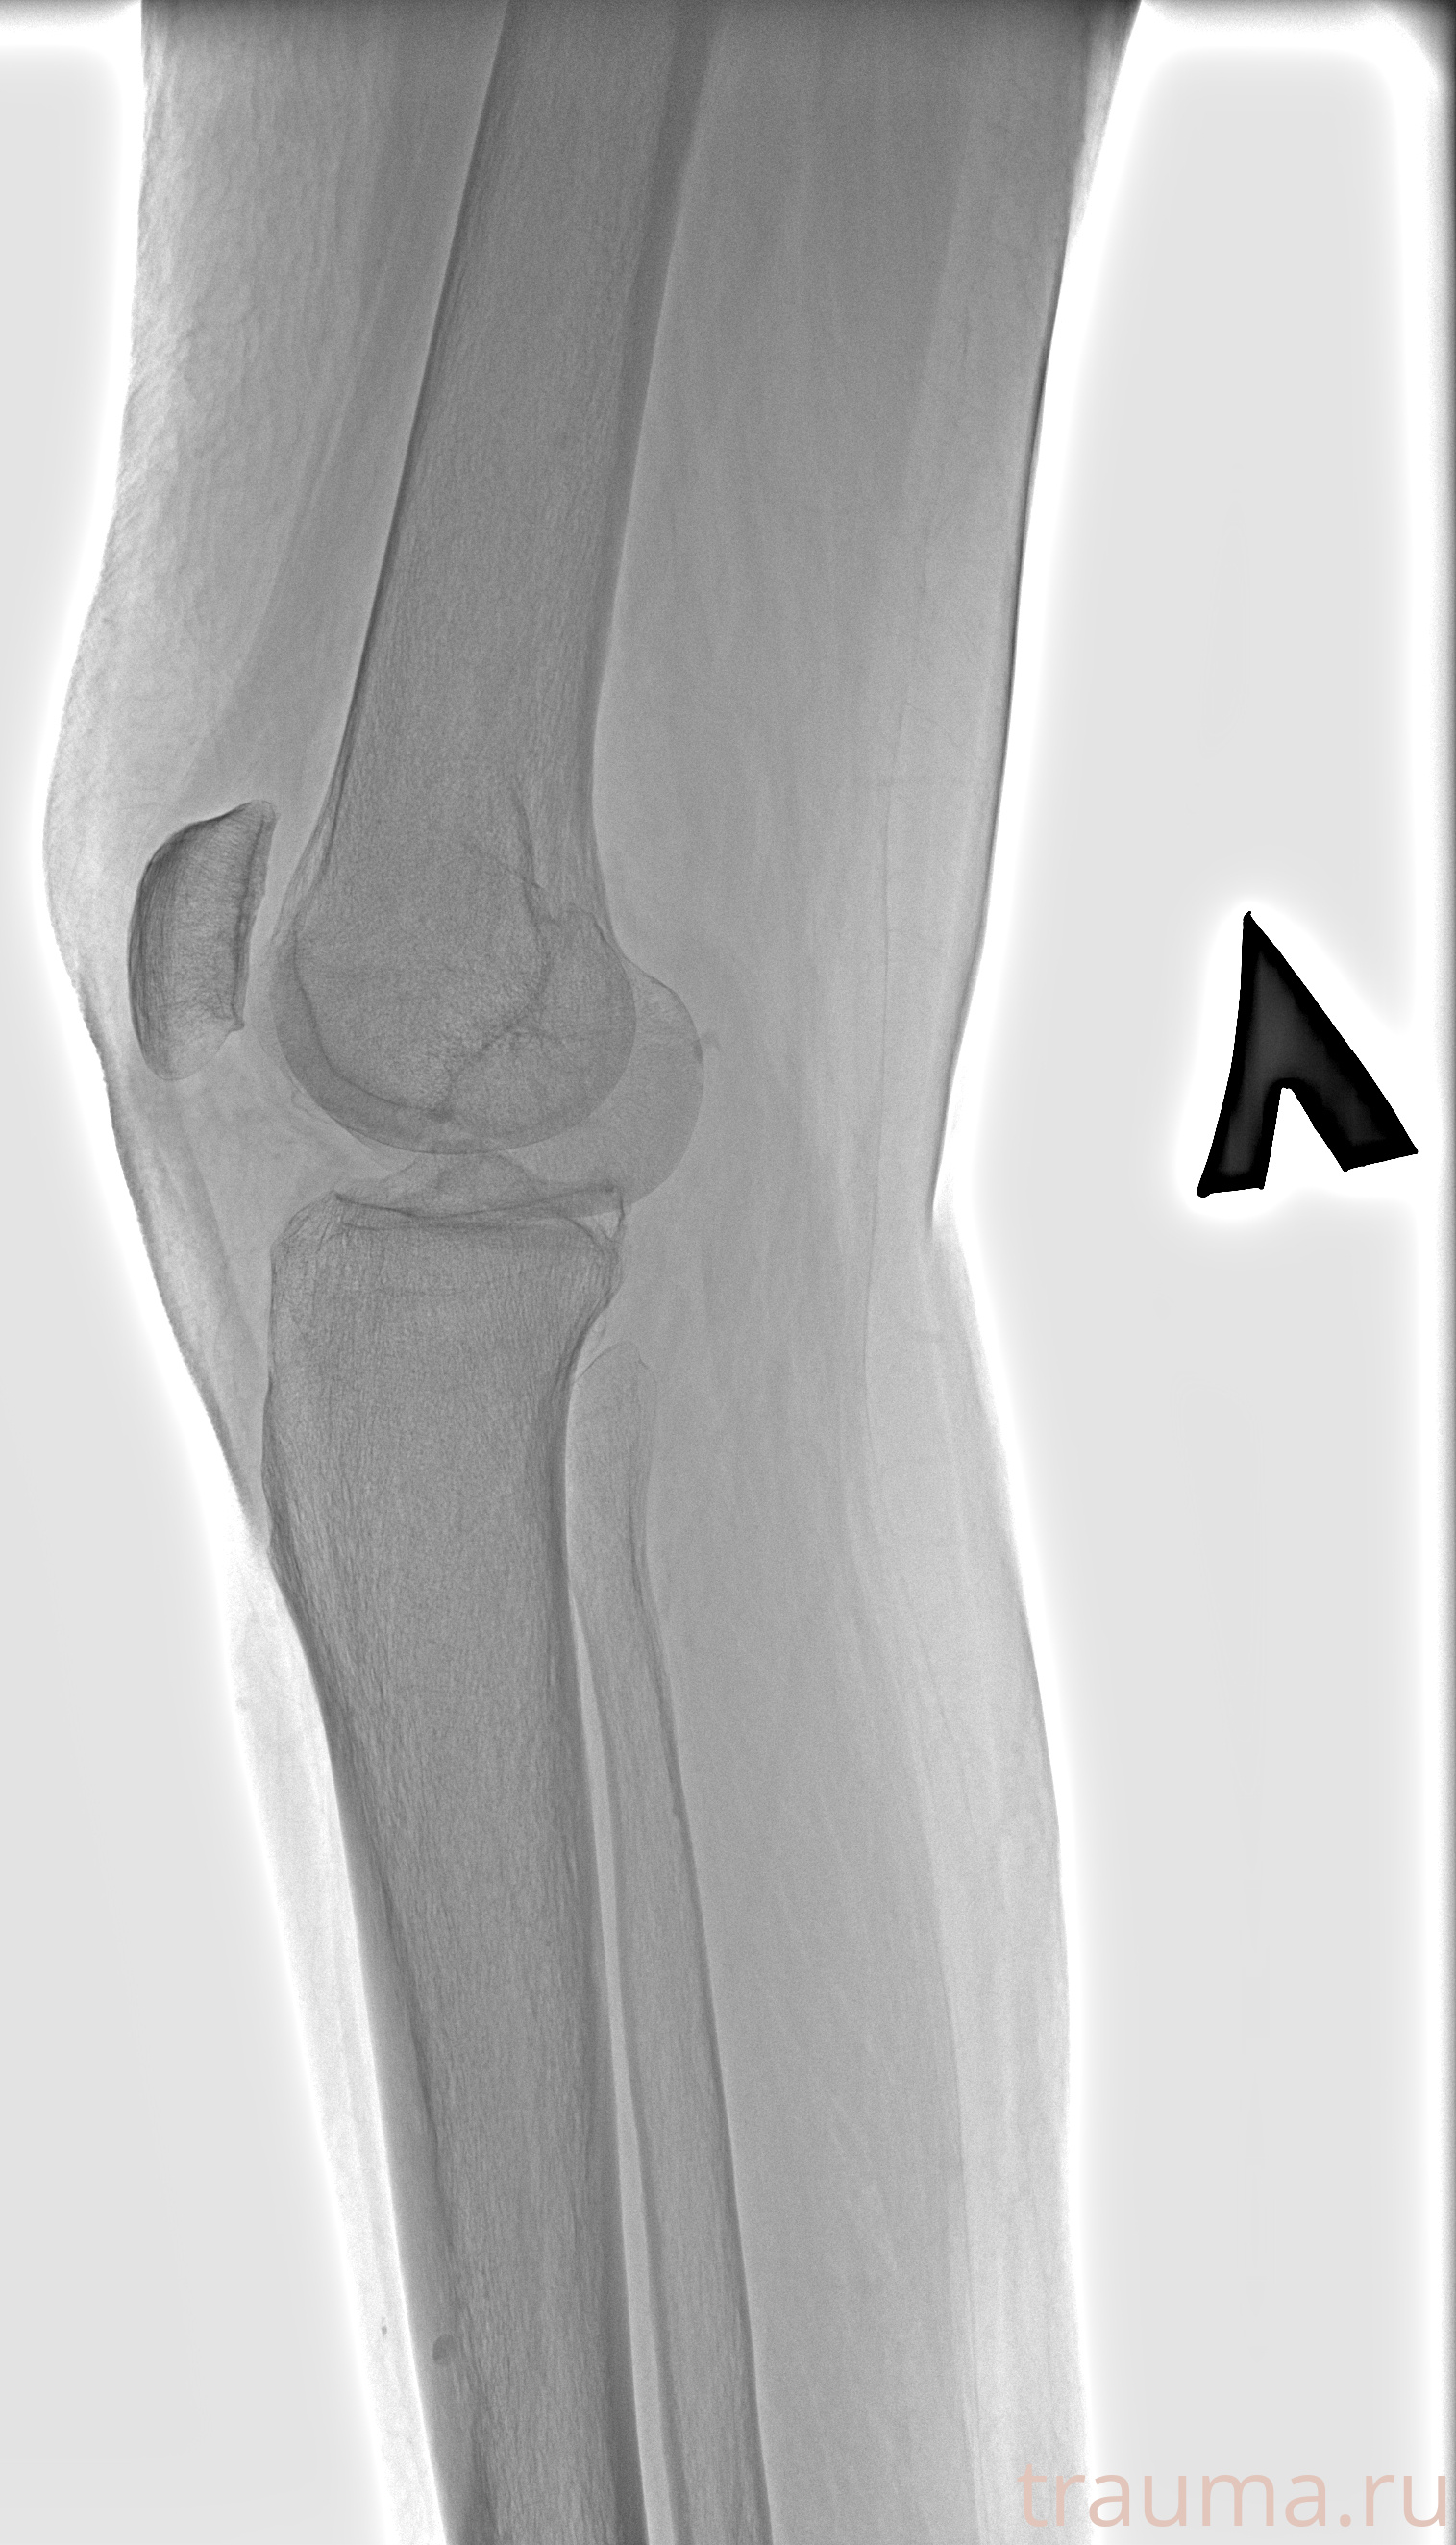

Рентгенограммы

Рентген на дому: по вашему адресу приезжает врач-рентгенолог, травматолог-ортопед с мобильным рентгеновским аппаратом, проводит диагностику травмы или заболевания, делает необходимые рентгенограммы, дает рекомендации по дальнейшему лечению. Получить качественные снимки в домашних условиях возможно благодаря уникальной методике, разработанной МосРентген Центром для института  Склифосовского